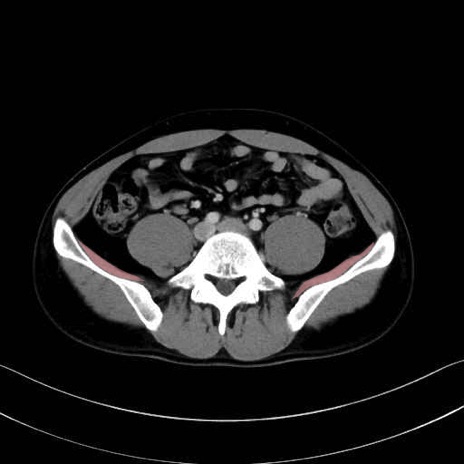

腸骨筋 (Iliacus)